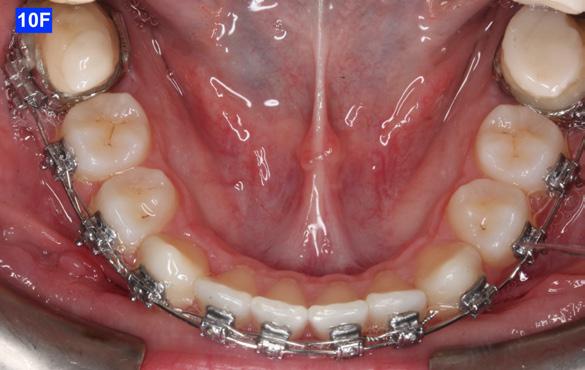

The final labial movement and de-rotation was done by the combined use of an Adrian “U” bend spring and an EC (a .016 SS and a .014 NiTi) (10 – D, E, F). When the maxillary lateral incisors settled in their proper site, the leveling of the maxillary arch was initiated. The progression of the arch wires was a .016 NiTi, a .0.18 NiTi, a .018 SS and the final arch wire, a .019 x .025 SS. There was only a .018 SS arch wire in the mandible. The remaining spaces were closed with a combination of the OCS, EC, and triangular elastics (1/4” – 4.5 oz) (Figure 11-A).

Class III inter-arch elastics (1/4” – 4.5 oz) were introduced to improve the inter-digitation (Figure 12 – A, B).

Three months before de-bracketing, while the patient had a .019 x .025 SS arch wire in the maxilla and the mandible, we appointed her for “Count down on retention.” The full arch wire was left in the maxilla, however, in the mandible, it was cut and bent-in, just distally to cuspids. Two triangular elastics were placed per sextant (1/4”– 4.5 oz.) for refinement of the tooth-to-tooth inter-digitation (Figure 13 - A, B, C).8

Figure 10E: Maxilla, occlusal view Figure 10F: Mandible, occlusal view Figure 11A: Frontal view Figure 12A: Class III elastic, right lateral view Figure 12B: Class III elastic, left lateral view Figure 11B: Goodman torquing spring Figure 11C: Goodman torquing spring in situ

Please view the post-treatment images at the time of insertion of the retainers (Figure 14 - A, B, C. D, E, F, G, H, I, J, K, L, M, N).9

Figure 14H: Post-treatment, mandible, occlusal view